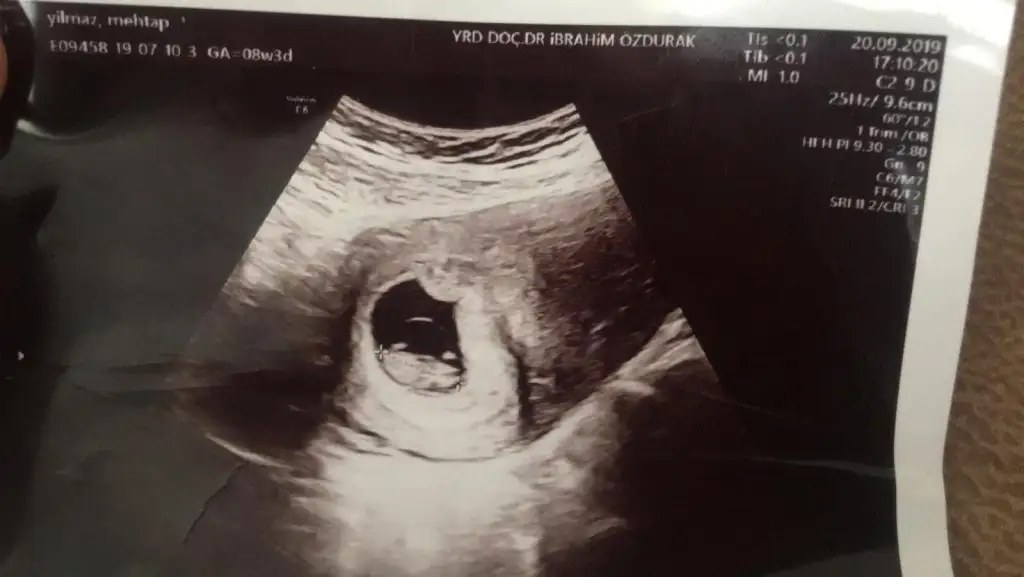

Merhaba hanımlar benim de 8+4 anlayanlar var ise yorumlayabilirmiRamzi teorisine göre ( bilimsel bir araştırma sonucuymuş ve %85 doğruluğu varmış). İlk 6-8 haftalık ultrason görüntüsüne göre bebeğin kesenin içersinde soldan ya da sağdan girişine göre cinsiyet tahmini yapılıyor. Bilimsel olunca tecrübeli annelerimiz yada anne adaylarımızdan yardım istiyoruz. Doğruluğu var mı öğrenmek adına :) Bizleri aydınlatırsanız çok seviniriz. bu teorieye göre;

Vajinal muayeneyle bakıldıysa eğer;

Sağdan girmiş gözüküyosa aslında solmuş ve ERKEK,

Soldan girmiş gözüküyosa aslında sağmış ve KIZ ,

Karından bakıldıysa eğer,

Soldan girmiş gözüküyosa gerçektede solmuş ve ERKEK,

Sağdan girmiş gözüküyosa gerçekte de sağmış ve KIZ,

Benim bebişime de bakarmısınızRamzi teorisine göre ( bilimsel bir araştırma sonucuymuş ve %85 doğruluğu varmış). İlk 6-8 haftalık ultrason görüntüsüne göre bebeğin kesenin içersinde soldan ya da sağdan girişine göre cinsiyet tahmini yapılıyor. Bilimsel olunca tecrübeli annelerimiz yada anne adaylarımızdan yardım istiyoruz. Doğruluğu var mı öğrenmek adına :) Bizleri aydınlatırsanız çok seviniriz. bu teorieye göre;